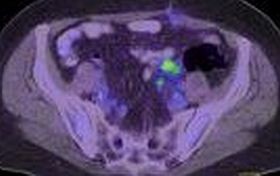

medencei-ct-felvetel-d00000E782680c0df35a6

"Az előzetes tudományos vizsgálat egy jövőbeni együttműködés első lépése, melynek eredményétől teszik függővé a további kutatási terveket" - olvasható az egyetem közleményében. A leleteket először hagyományos módszerekkel vizsgálják meg a kutatók a múzeumban, majd a múmiákat az egyetemre szállítják. A sterilitás szabályait szem előtt tartva egyenként vetik alá a computer-tomográfiai (CT) vizsgálatnak.

A leletekről így háromdimenziós, a további kutatások szempontjából jól használható modellek készülnek, ezek képezik majd a Szépművészeti Múzeum 2011 júniusára tervezett kiállításának gerincét.

Mint írták, a CT-vizsgálatok felvételei alapján olyan háromdimenziós modellek készülnek, amelyek segítségével a múmiák a későbbiekben anélkül lesznek vizsgálhatóak a kutatók számára, és bemutathatóak a múzeumi nagyközönségnek, hogy a szigorúan klimatizált környezetben tartott eredeti testeket újból mozgatnák.